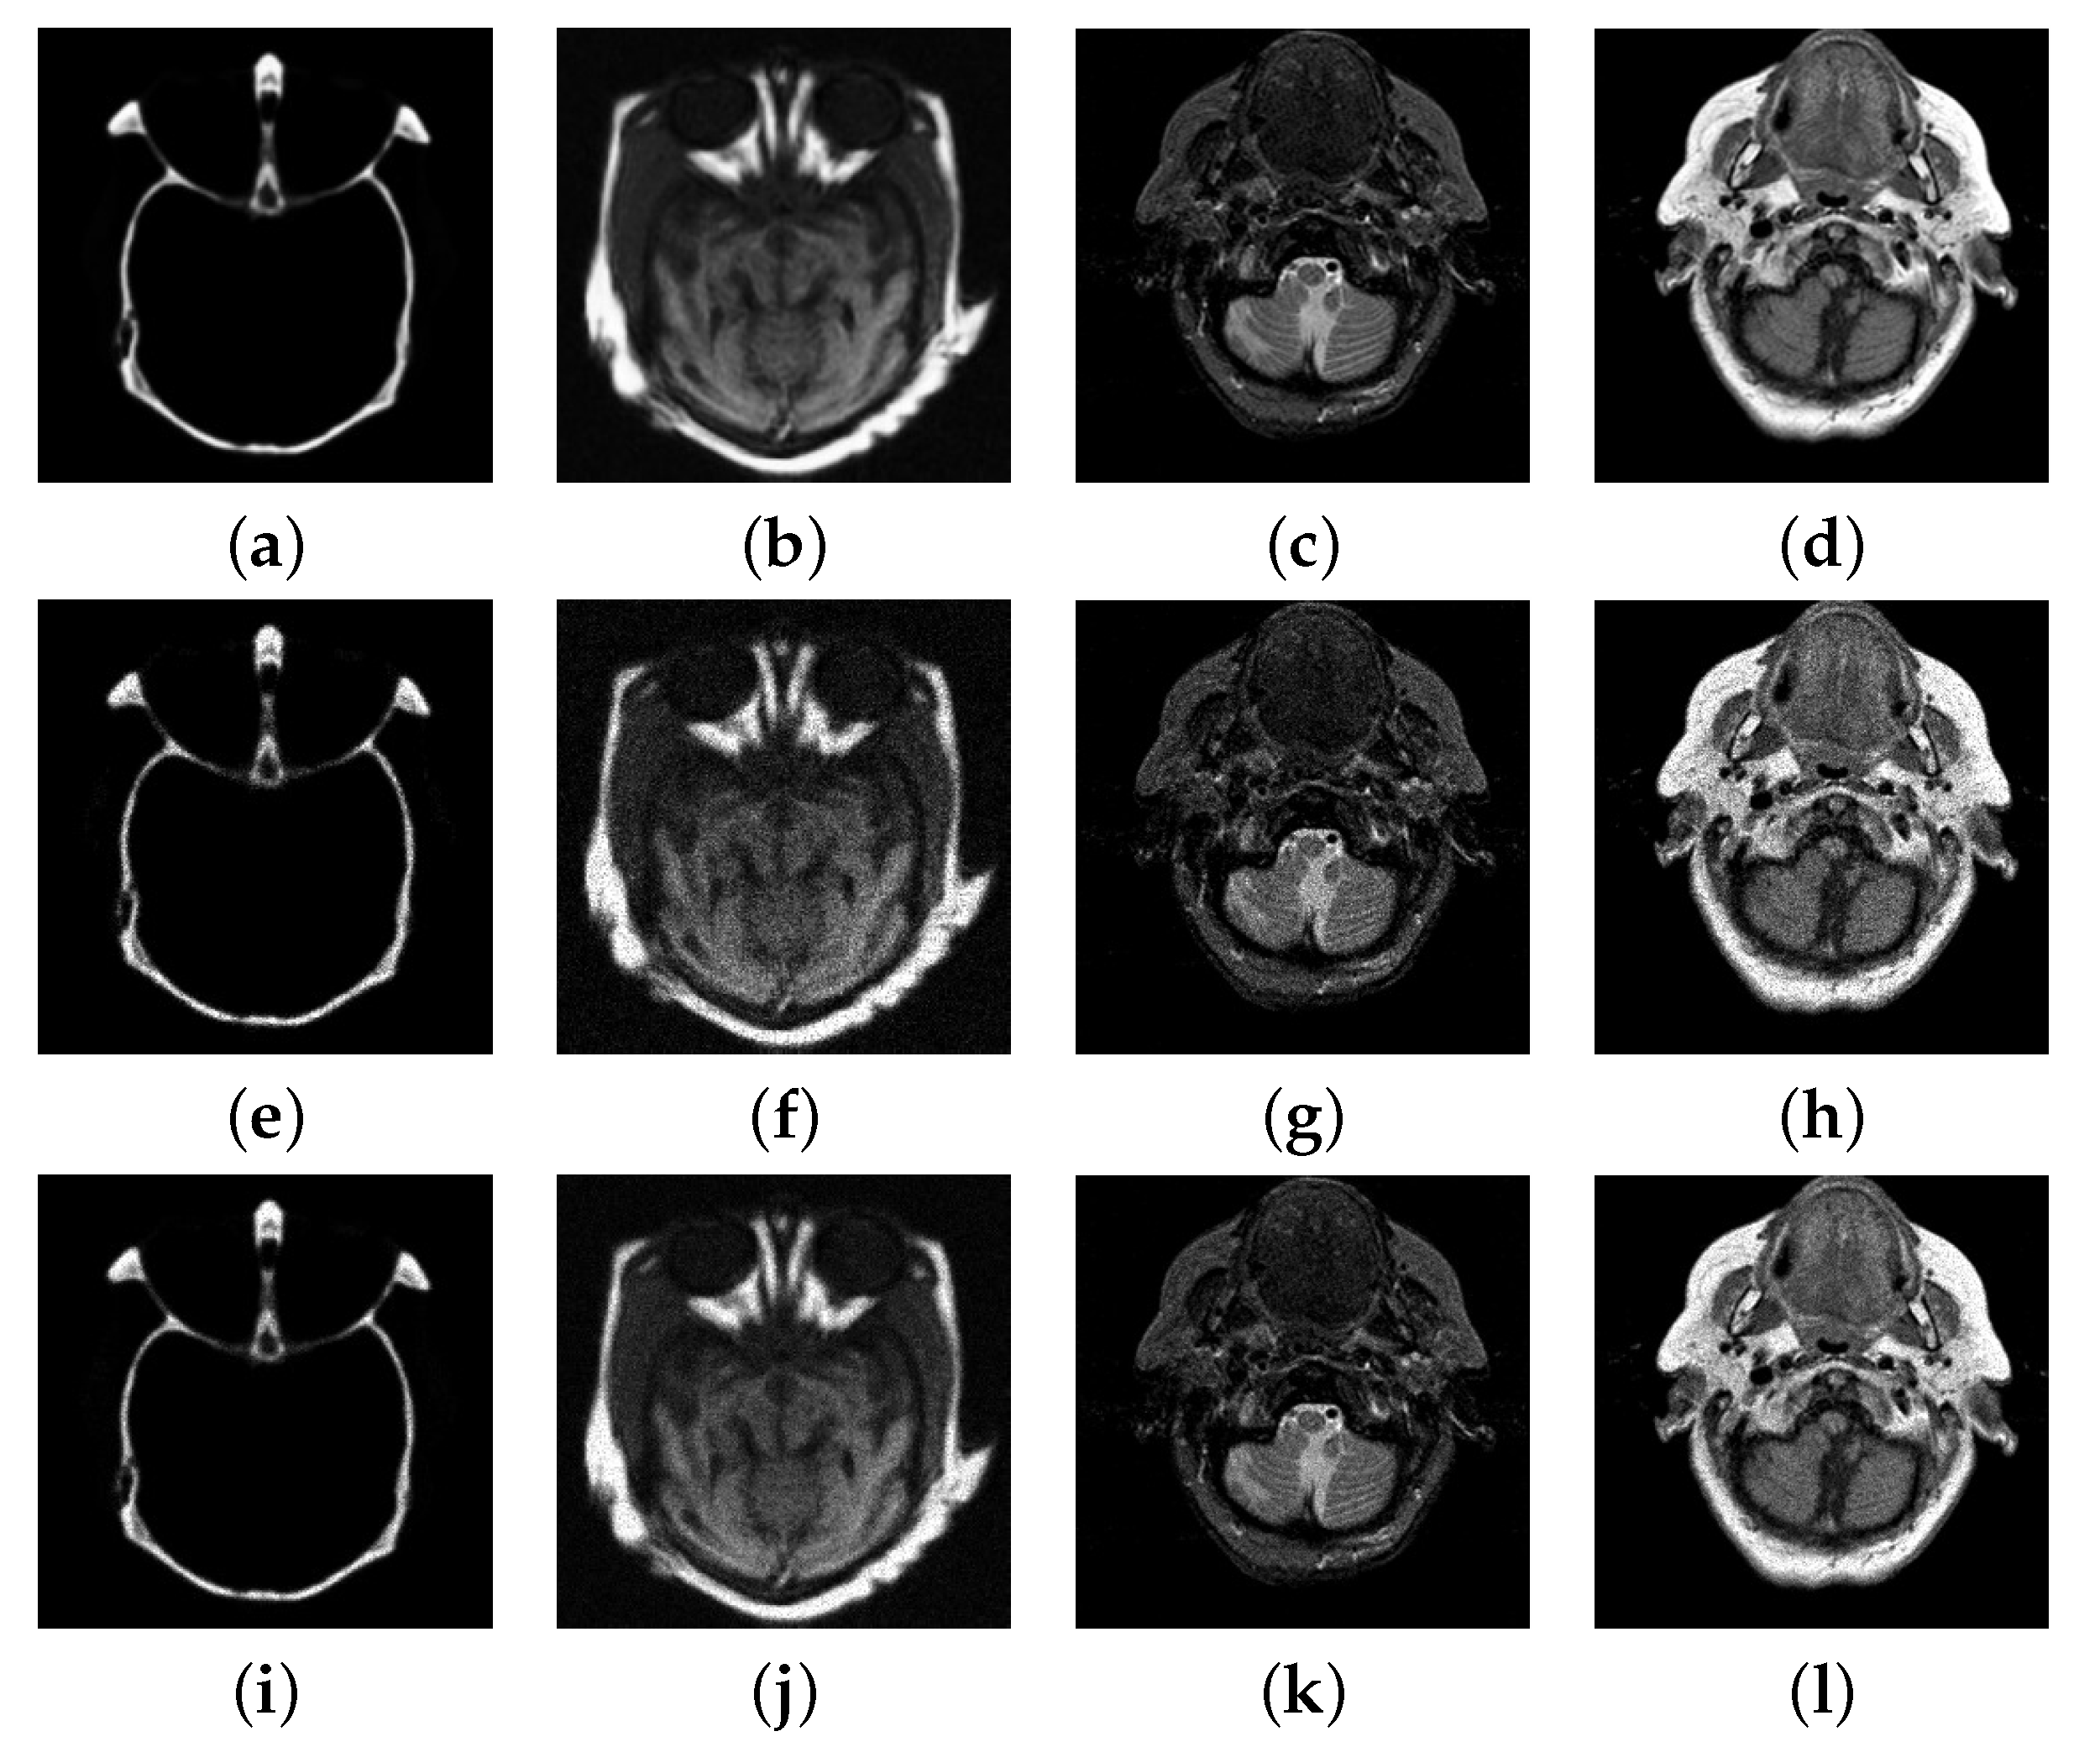

4.3. Numerical Experimental Results and Analysis